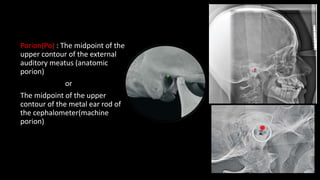

Porion(Po) : The midpoint of the

upper contour of the external

auditory meatus (anatomic

porion)

or

The midpoint of the upper

contour of the metal ear rod of

the cephalometer(machine